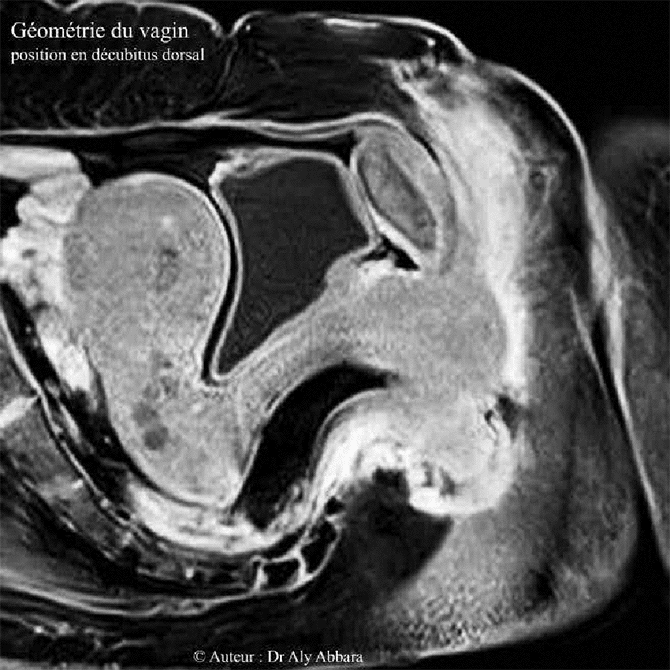

Vagin de femme adulte - L'arc anatomique - IRM

On observe sur cette image que l'axe du vagin n'est pas une ligne droite : il prend la forme d'un arc dessinant

un angle obtus dirigé vers l'arrière d'environ 140°.

• Morphologiquement le vagin est plus étroit au niveau de son tiers inférieur, près de la vulve, puis il s'élargit au niveau de son tiers moyen et surtout au tiers supérieur, cette étroitesse relative dans la portion vaginale située près de son entrée vulvaire est due à la présence des fuseaux musculaires des muscles releveurs de l'anus qui encerclent cette partie du vagin en arrière et bilatéralement. Cet encerclement musculaire donne au vagin une forme coudée ou arquée, donc en position décubitus dorsal, sur un plan sagittal médian, la partie basse du vagin est oblique (de l'arrière en bas vers l'avant en haut), la partie haute du vagin se dirige vers l'arrière. L'angle formé (ou l'arc) par les deux axes du vagin est un angle obtus, ouvert vers le bas (en position allongée sur le dos) et sa valeur est égale à environ à 140 degrés.